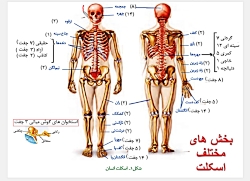

عکس اسکلت بدن انسان با کیفیت. عکس اسکلت عکس اسکلت برای پروفایل عکس اسکلت انسان عکس اسکلت خفن عکس اسکلت بدن انسان با کیفیت عکس اسکلت بدن انسان عکس اسکلت ترسناک عکس اسکلت فانتزی عکس اسکلت فانتزی دخترانه پرچم عکس اسکلت. عکس با کیفیت اسکلت داخلی انسان و درد و گرفتگی در ناحیه استخوان زانو ویژه استفاده در امور تبلیغاتی و تجاری طراحی کاتالوگ بروشور و تراکت با موضوع پزشکی فیزیوتراپی ارتوپد دکتر روماتیسم فیریوتراپ طب فیزیکی. عکس اسکلت بدن انسان زن و مرد آناتومی ساتین 16 سپتامبر 2017. اسکلت داربست بدن است تمام قسمت های بدن روی اسکلت قرارگرفته اند بدن انسان از ۲۰۶ قطعه استخوان تشکیل شده است این استخوان ها طوری با نظم کنار هم قرار گرفته اند که انسان را قادر می سازد حرکات دقیقی داشته باشد.

اسکلت جمجمه و گردن انسان ستون فقرات آناتومی اسکلت جمجمه و گردن انسان ستون فقرات آناتومی تصویر با کیفیت را از لینک زیر می توانید دانلود کنید. ۱ مطلب با کلمه ی کلیدی عکس اسکلت بدن انسان با کیفیت ثبت شده است گالری نسیم جدید ترین و با کیفیت ترین عکس های مناسبتی. عکس با کیفیت آناتومی اسکلت بدن انسان و درد و دیسک در قسمت مهره های ستون فقرات کمر ویژه استفاده در امور تبلیغاتی و تجاری طراحی کاتالوگ بروشور و تراکت با موضوع بیمارستان ها و کلینیک ها و درمانگاه ها و مطب ها پزشکان و.